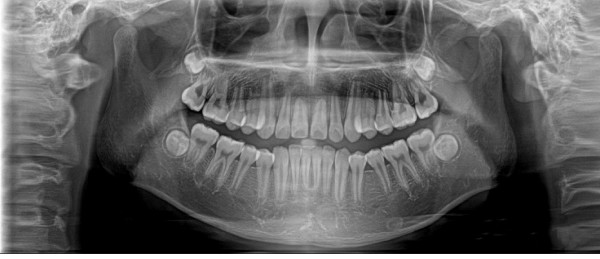

全景機(jī)基于體層攝影原理設(shè)計(jì)而成,全景攝影時(shí),根據(jù)口腔頜面部的解剖特點(diǎn),X線(xiàn)球管?chē)@人體頭部選擇約120°,從一側(cè)顳下頜關(guān)節(jié)到另一側(cè)顳下頜關(guān)節(jié),最后一次性獲得全口牙齒的2D圖像,使頜骨及全口牙體層攝影在一幅圖片上呈現(xiàn)左右展開(kāi)的平面圖。

全景機(jī)具有觀(guān)察全面、操作簡(jiǎn)便、兒童及老弱患者容易接受的優(yōu)點(diǎn)。然而,全景機(jī)的缺點(diǎn)也非常明顯:

1.相較牙片機(jī),全景成像中牙齒內(nèi)部的清晰度和細(xì)節(jié)明顯要略遜一籌;

2.由于是曲線(xiàn)體層成像,其圖像有比較嚴(yán)重的畸變失真,同樣也不可避免的具有影像重疊。

因此,全景機(jī)主要用于觀(guān)察所有牙齒的形態(tài)、位置及頜骨內(nèi)情況,為牙齒正畸矯正、牙齒修復(fù)提供圖像依據(jù),不太適合用于對(duì)牙齒結(jié)構(gòu)成像清晰度要求非常高的領(lǐng)域。